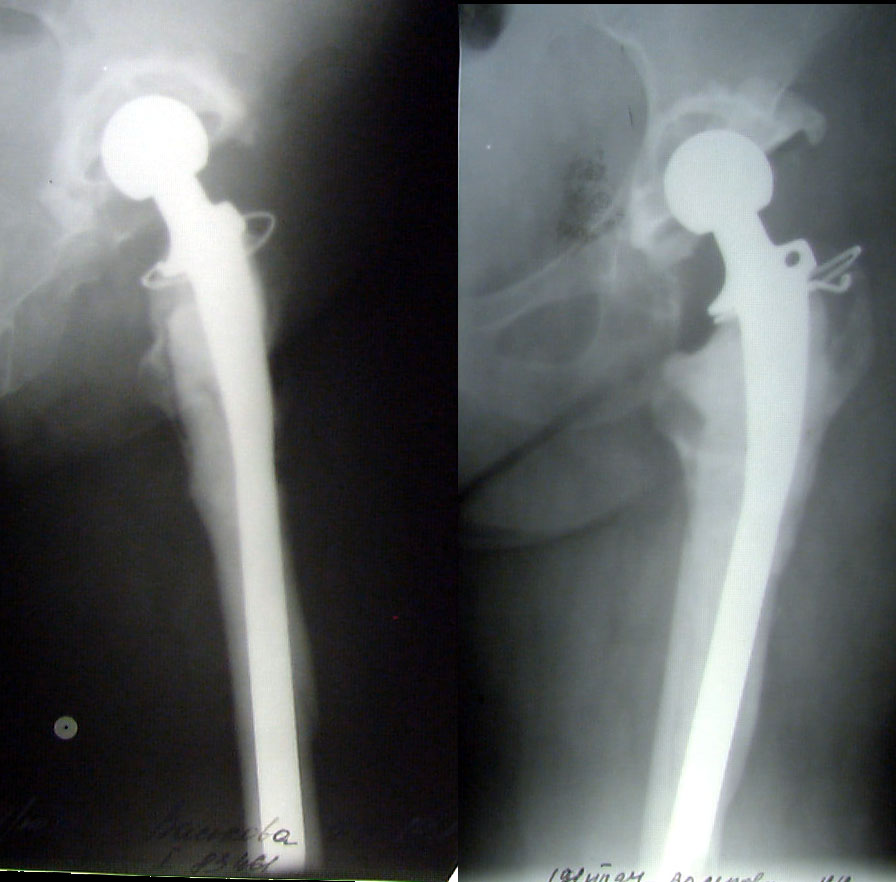

ÊÎÑÒÍÎÏËÀÑÒÈ×ÅÑÊÎÅ ÓÊÐÅÏËÅÍÈÅ ÂÅÐÒËÓÆÍÎÉ ÂÏÀÄÈÍÛ ÏÐÈ ÒÎÒÀËÜÍÎÌ ÝÍÄÎÏÐÎÒÅÇÈÐÎÂÀÍÈÈ ÏÎ ÏÎÂÎÄÓ ÄÈÑÏËÀÑÒÈ×ÅÑÊÎÃÎ ÊÎÊÑÀÐÒÐÎÇÀ ÊÎÑÒÍÎÏËÀÑÒÈ×ÅÑÊÎÅ ÓÊÐÅÏËÅÍÈÅ ÂÅÐÒËÓÆÍÎÉ ÂÏÀÄÈÍÛ ÏÐÈ ÒÎÒÀËÜÍÎÌ ÝÍÄÎÏÐÎÒÅÇÈÐÎÂÀÍÈÈ ÏÎ ÏÎÂÎÄÓ ÄÈÑÏËÀÑÒÈ×ÅÑÊÎÃÎ ÊÎÊÑÀÐÒÐÎÇÀ Âîëîøèí Â.Ï., Ìàðòûíåíêî Ä.Â., ÌÎÍÈÊÈ, Ìîñêâà, Ðîññèÿ

Êàðòèíêà Êàðòèíêà